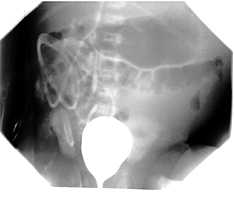

Niña de 8 años con historia de infecciones urinarias de repetición secundarias a un reflujo vesico-ureteral de grado IV.